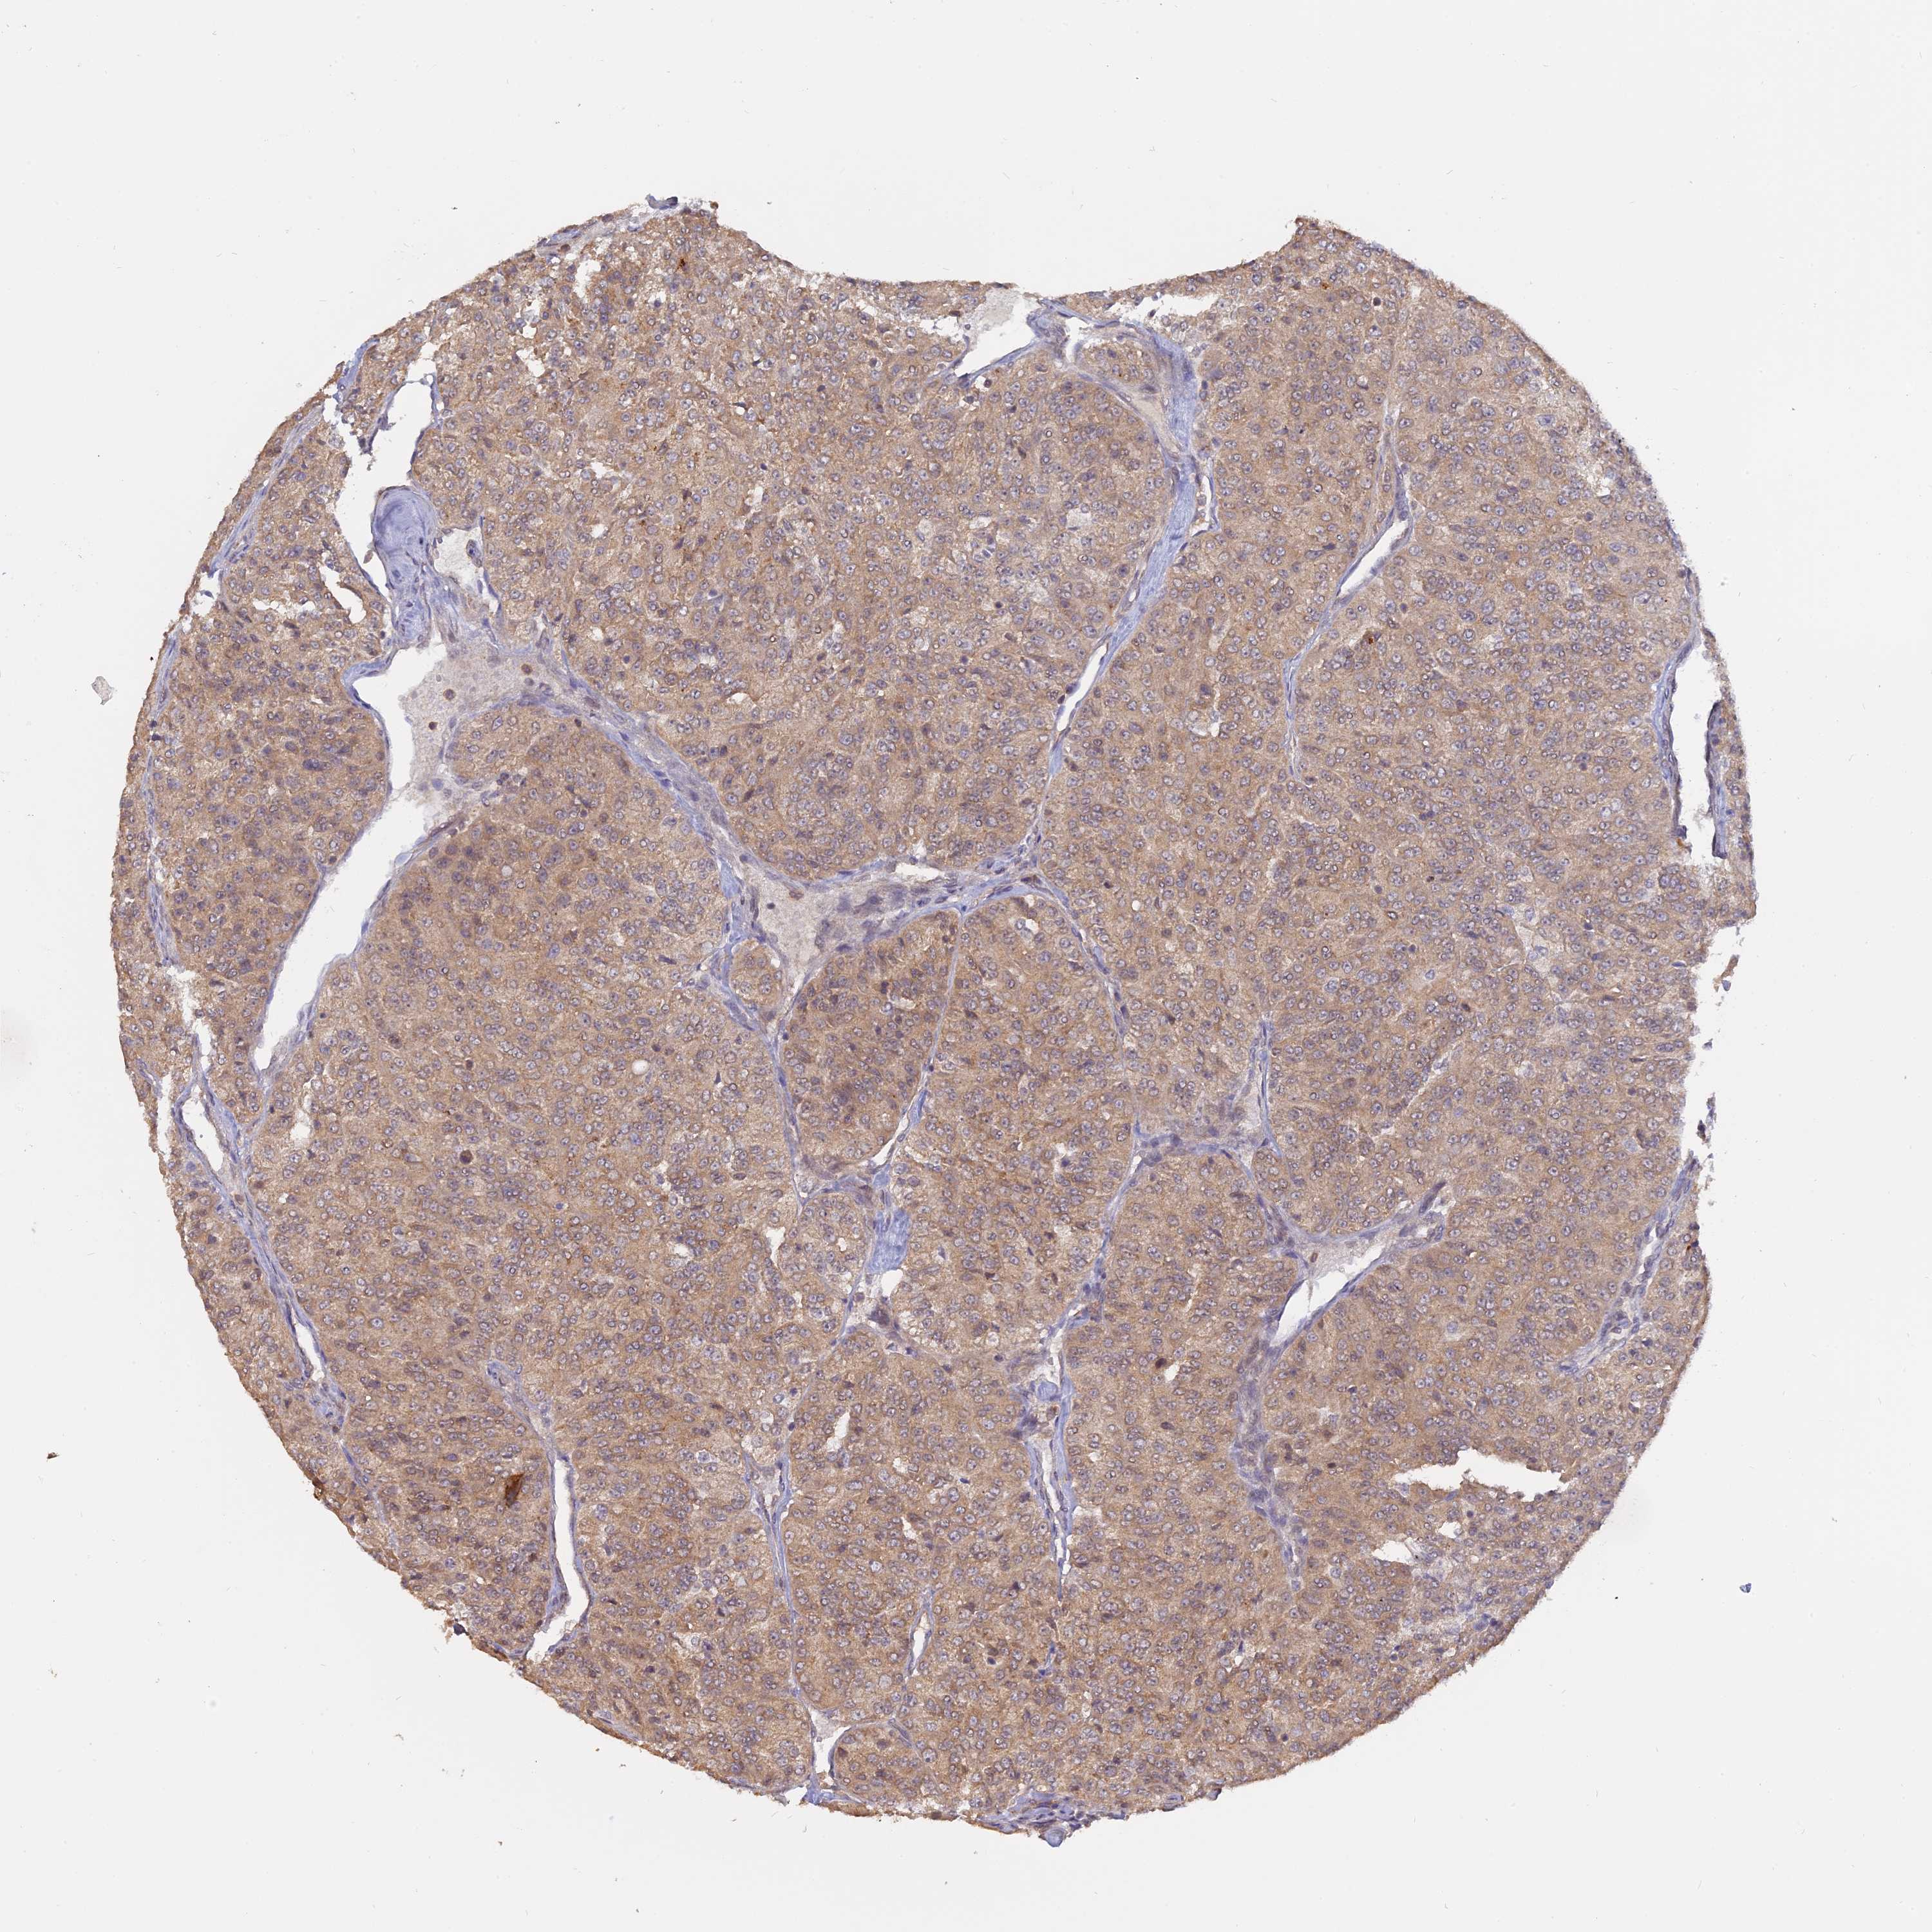

KIDNEY RENAL PAPILLARY CELL CARCINOMA (TCGA) - Interactive survival scatter ploti

The Survival Scatter plot shows the clinical status (i.e. dead or alive) for all individuals in the patient cohort, based on the same data that underlies the corresponding Kaplan-Meier plots. Patients that are alive at last time for follow-up are shown in blue and patients who have died during the study are shown in red.

The x-axis shows the expression levels (FPKM) of the investigated gene in the tumor tissue at the time of diagnosis. The y-axis shows the follow-up time after diagnosis (years). Both axes are complimented with kernel density curves demonstrating the data density over the axes. The top density plot shows the expression levels (FPKM) distribution among dead (red) and alive patients (blue). The right density plot shows the data density of the survived years of dead patients with high and low expression levels respectively, stratified using the cutoff indicated by the vertical dashed line through the Survival Scatter plot. This cutoff is automatically defined based on the FPKM cutoff that minimizes the p-score. The cutoff can be changed by dragging the vertical line or by entering a cutoff value in the square labeled "Current cut-off".

Under the Survival Scatter plot the p-score landscape (black curve; left axis) is shown together with dead median separation (red curve; right axis). Dead median separation is the difference in median mRNA expression between patients who have died with high and low expression, respectively. It is calculated as follows: median FPKM expression of dead patients with high expression - median FPKM expression of dead patients with low expression. This is intended to aid the user in visually exploring custom cutoffs and the associated p-scores and dead median separation.

Individual patient data is displayed and can be filtered by clicking on one or more of the category buttons on the top of the page. Categories describing expression level and patient information include: high, low, alive, dead, female, male and tumor stages. The scale of the x-axis can be toggled between linear and log-scale by clicking on the "x log" button. Mouse-over function shows TCGA ID, patient information and mRNA expression (FPKM) for each patient.

& Survival analysisi

Kaplan-Meier plots summarize results from analysis of correlation between mRNA expression level and patient survival. Patients were divided based on level of expression into one of the two groups "low" (under cut off) or "high" (over cut off). X-axis shows time for survival (years) and y-axis shows the probability of survival, where 1.0 corresponds to 100 percent.

PKIG is potential prognostic, high expression is favorable in Kidney Renal Papillary Cell Carcinoma (TCGA)